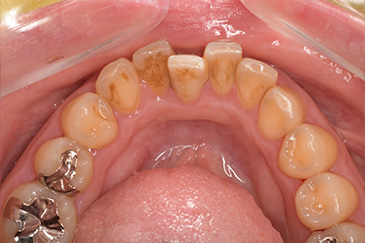

CASE 5

Before

After

基本情報

| 年齢・性別 | 19歳・女性 |

|---|---|

| 主訴 | 定期検診 |

| 治療内容 | PMTC |

| 治療期間 | 30分 |

| 治療費 | 5,500円 |

| リスク・副作用 | 知覚過敏 |

| 治療方針 | スケーリングしてから着色を除去しました。着色は一度綺麗に落としても再度付着するため、今後は定期的なクリーニングを行います。 |

| 担当者所見 | 歯ぐきに色素が沈着しているためガムピーリングとホワイトニングを行うことで、より明るく見えるようになります。 |